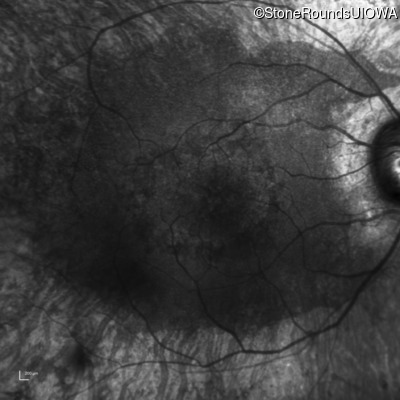

Infrared Fundus Photograph - Left - 20/125

Exemplar